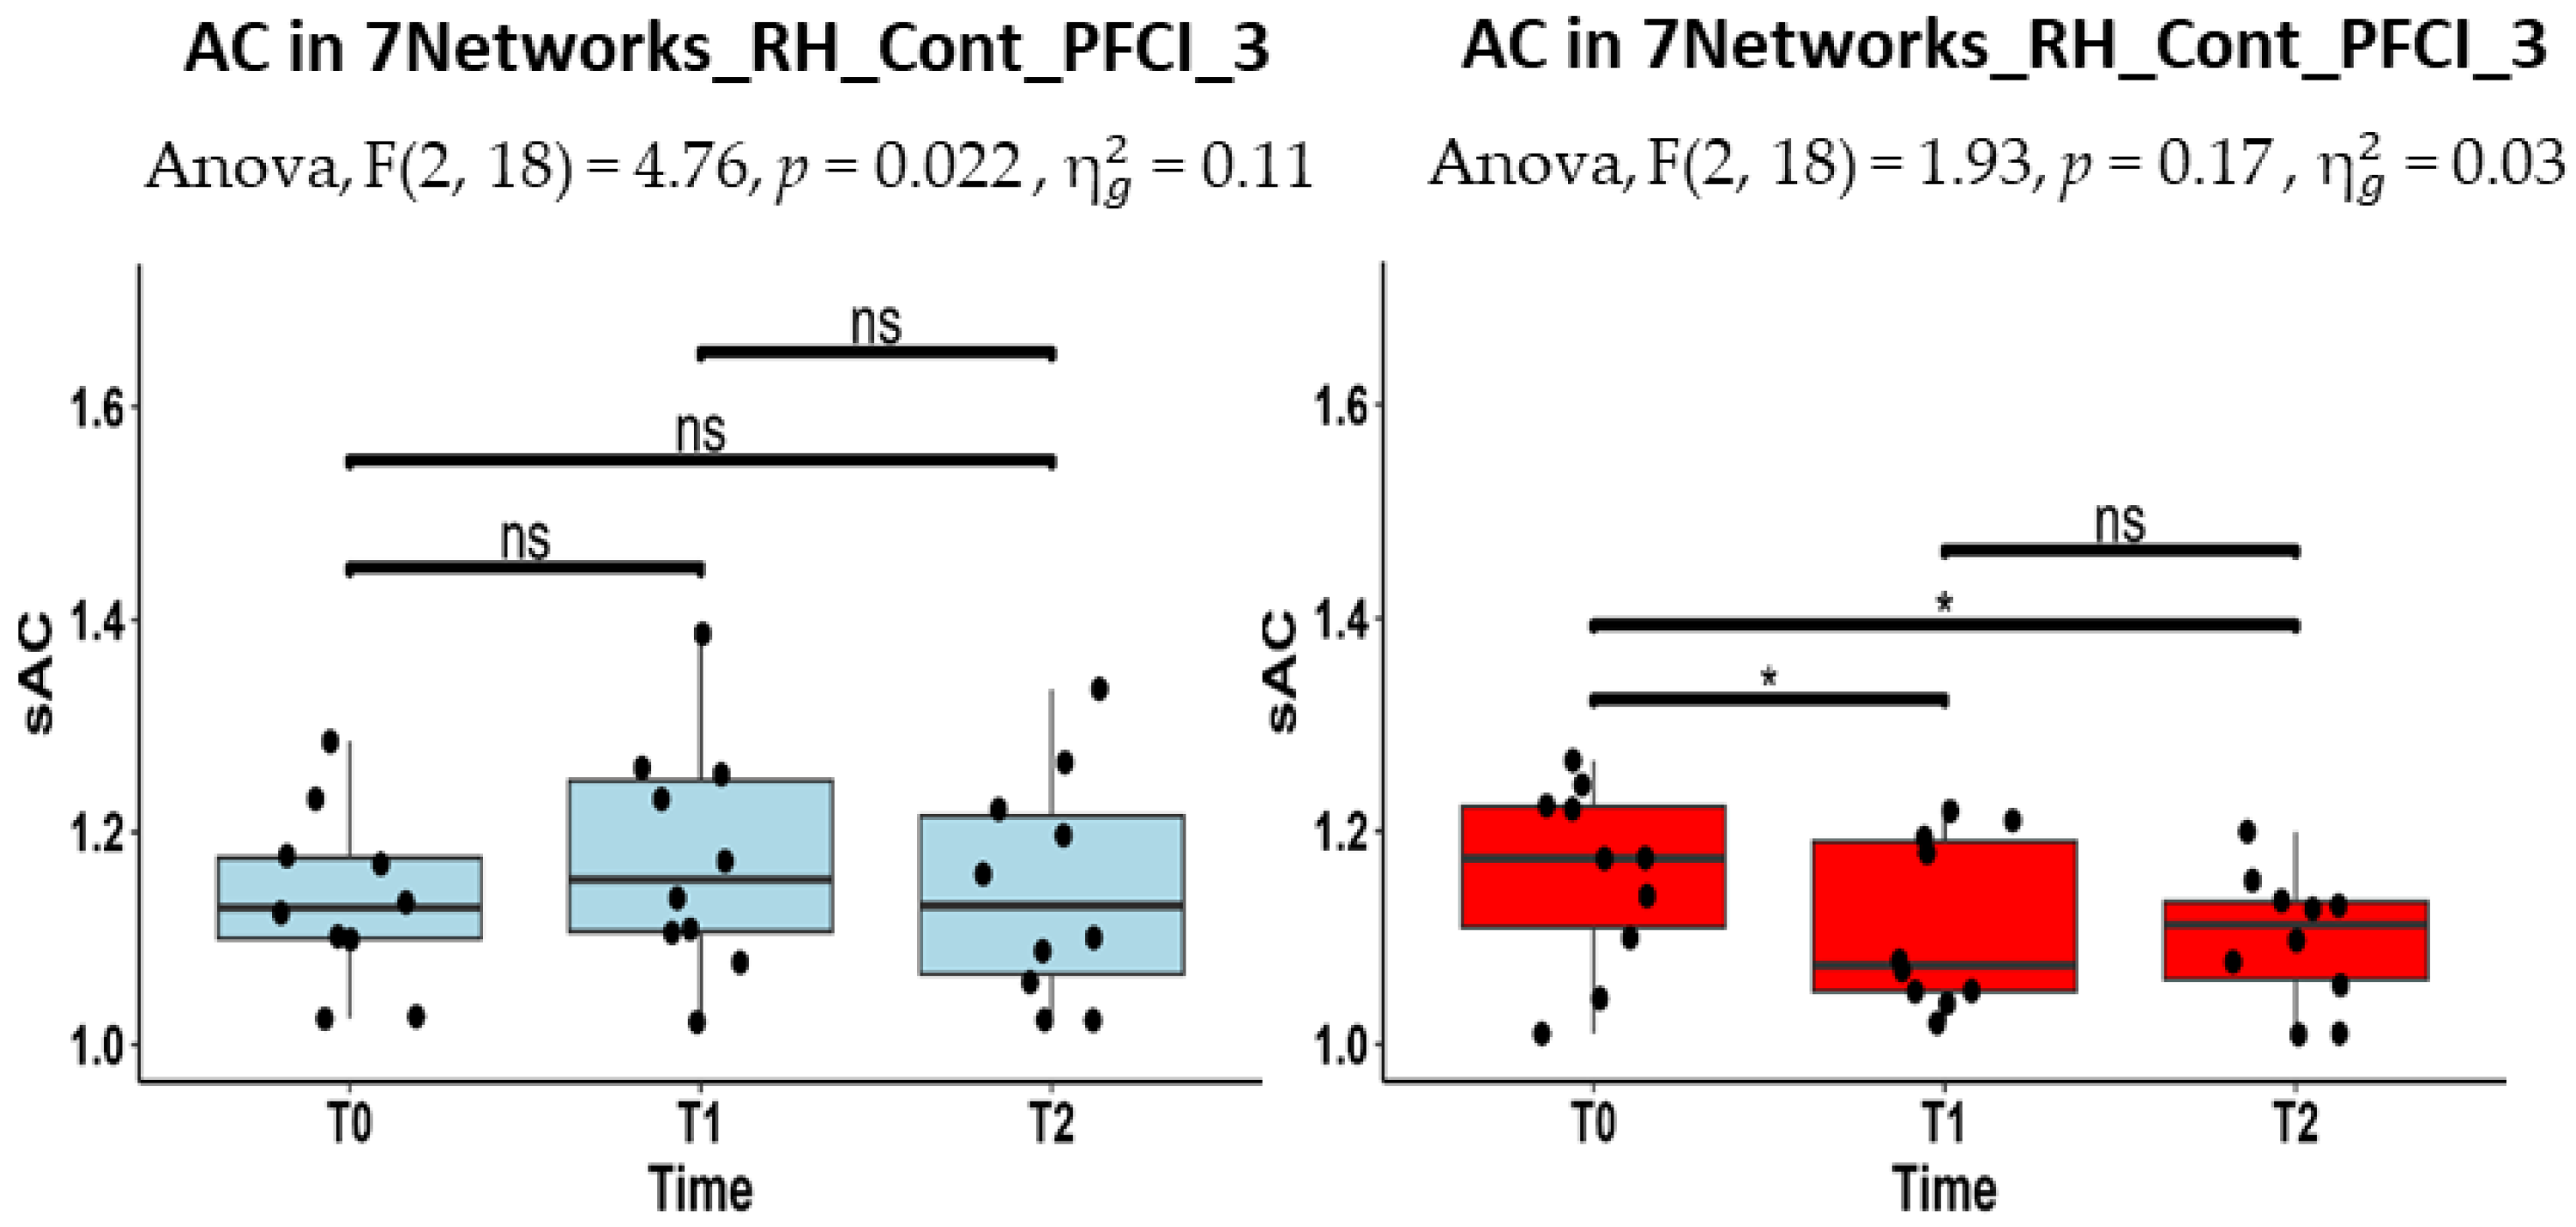

| RH_Cont_PFCl_3 | 1.13 (1.10–1.18) | 1.16 (1.11–1.25) | 1.13 (1.07–1.22) |

| RH_Cont_PFCl_4 | 1.19 (1.12–1.22) | 1.21 (1.14–1.25) | 1.21 (1.07–1.30) |

| RH_Cont_PFCl_3 | 1.17 (1.11- 1.22) | 1.07 (1.05–1.19) | 1.11 (1.06–1.13) |

| RH_Cont_PFCl_4 | 1.17 (1.11–1.24) | 1.10 (1.04–1.15) | 1.10 (1.04–1.20) |